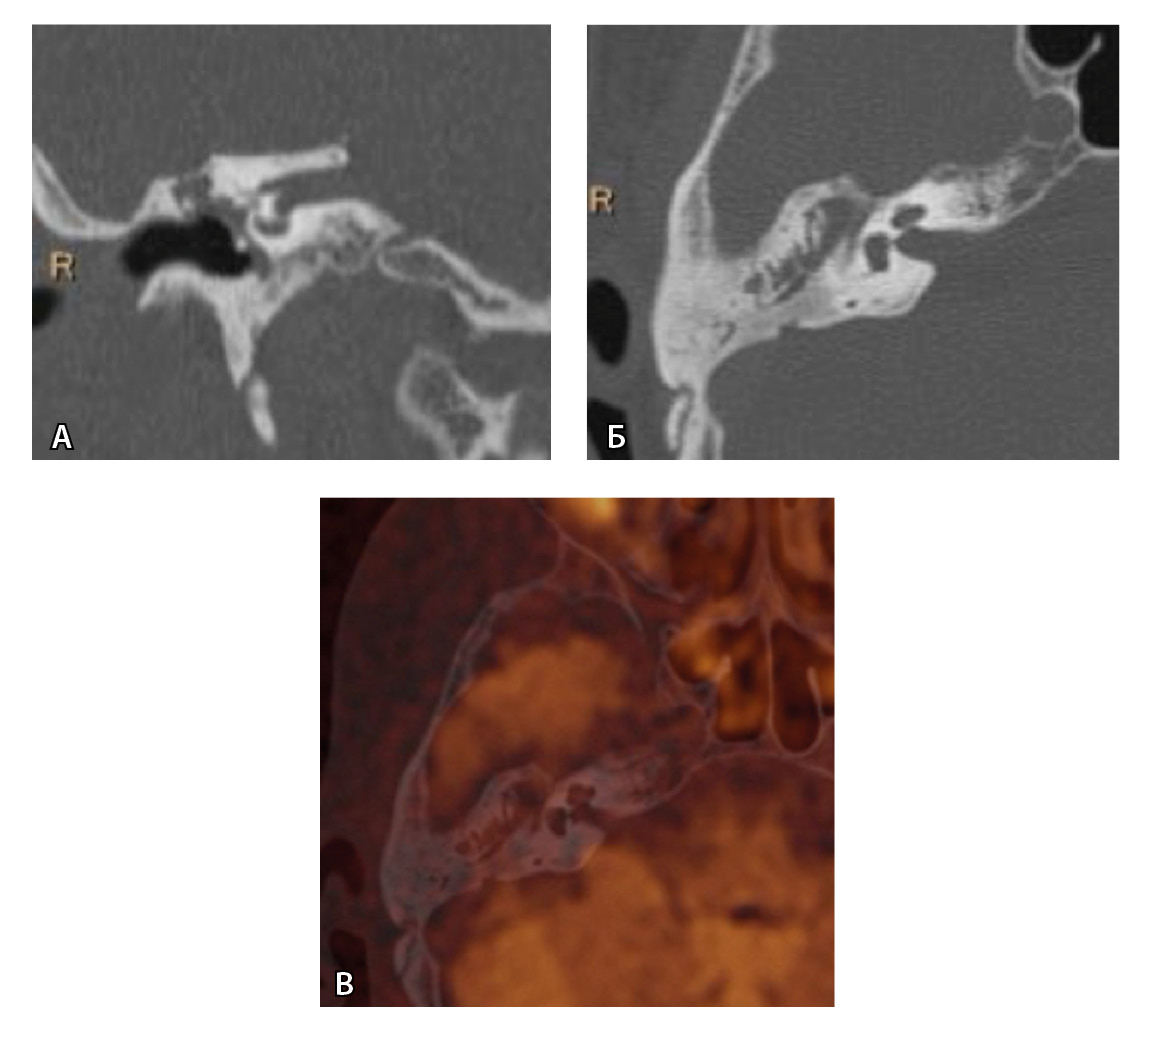

Для слияния изображений выбирались пациенты, у которых были выполнены обе модальности – КТ и МРТ – и только те исследования, где при МРТ определялось ограничение диффузии и его локализация могла соответствовать холестеатоме – впервые выявленной или рецидивной. Были совмещены 236 пар исследований ушей (КТ и МРТ) с МР-картиной высокого МР-сигнала при диффузии (рис. 2).

Рис. 2. На совмещенных КТ- и МР-изображениях видна мелкая рецидивная холестеатома в барабанной части послеоперационной полости. При этом четко видна и сама холестеатома, и ее локализация относительно стенок полости, и ее взаимоотношения с другими важными костными структурами, в том числе каналом лицевого нерва